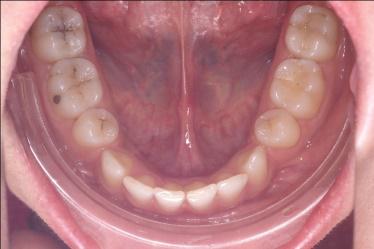

La technique linguale

Totalement invisible les attaches orthodontiques sont collées sur la face linguale